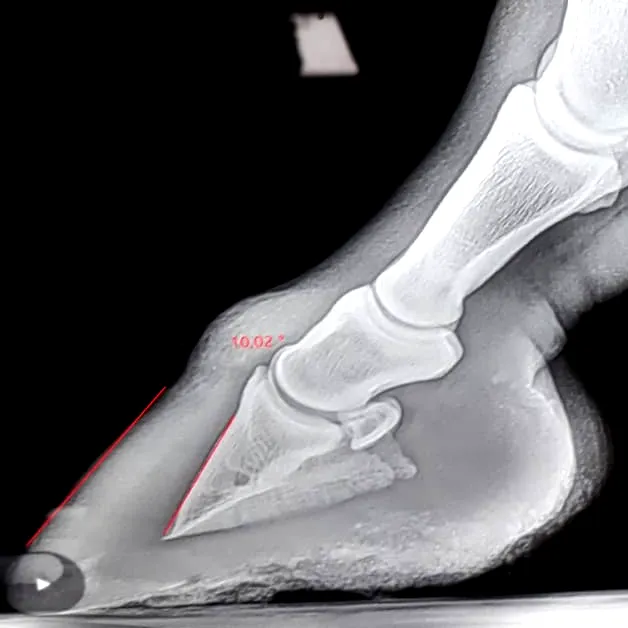

Warum Röntgen Pflicht ist

Nur eine Röntgendiagnostik zeigt eindeutig:

Ob eine Hufbeinrotation vorliegt

Ob eine Hufbeinabsenkung geschehen ist

Wie stark die Schädigung ist

Alles andere ist Spekulation – und kostet wertvolle Zeit, in der sich der Zustand rapide verschlechtern kann.